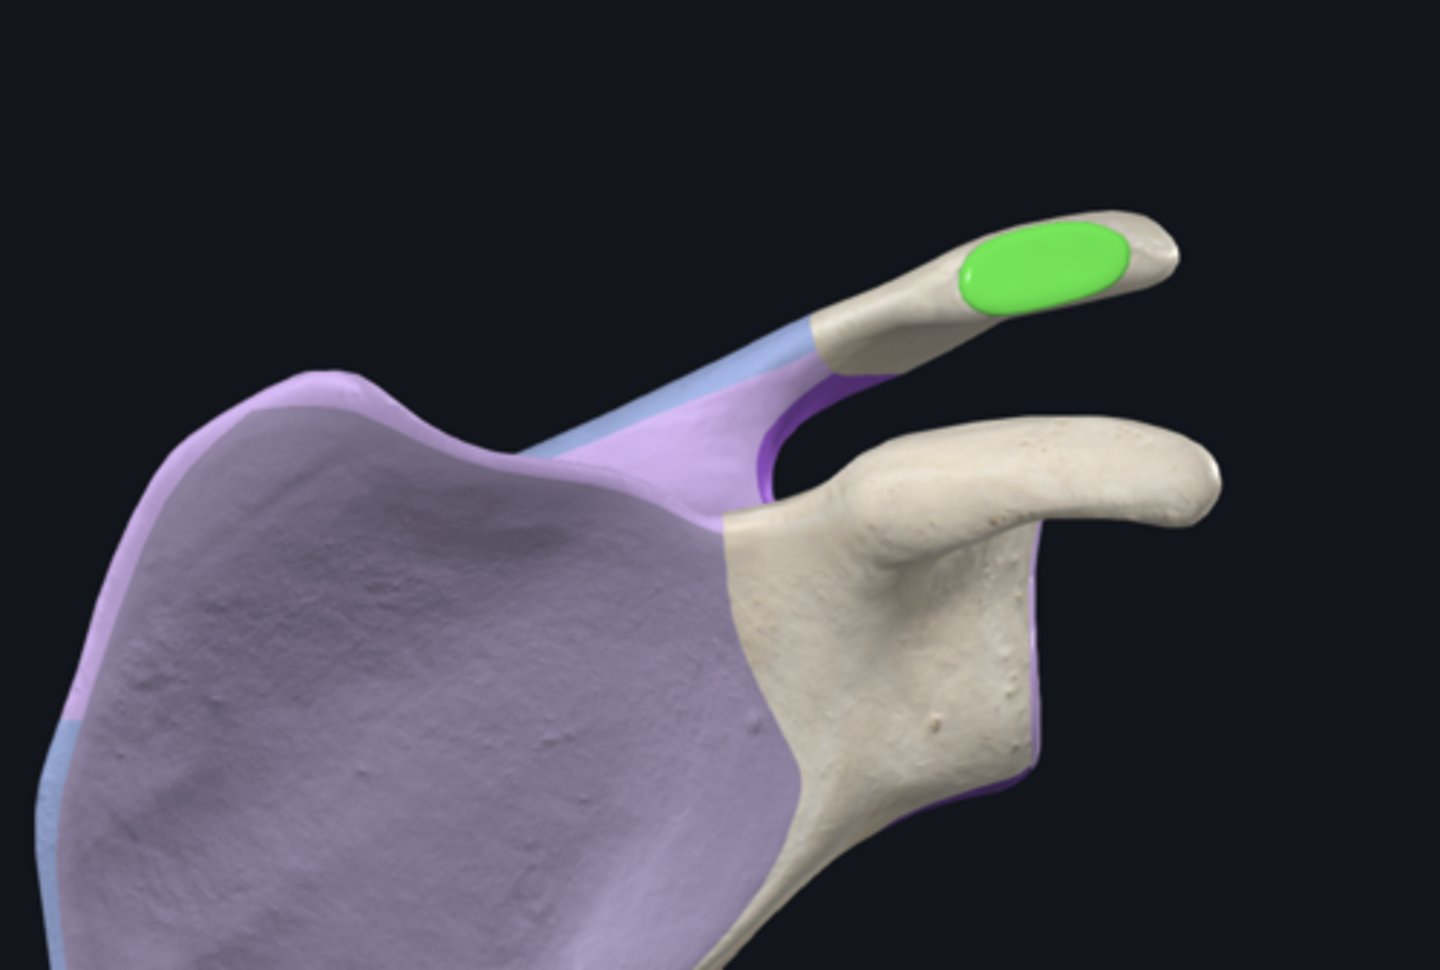

acromial end

body of clavicle

sternal end

anterior border of clavicle

inferior surface of clavicle

posterior border of clavicle

superior surface of clavicle

acromial facet

conoid tubercle

groove for subclavius muscle

impression for costoclavicular ligament

sternal articular surface

trapezoid line